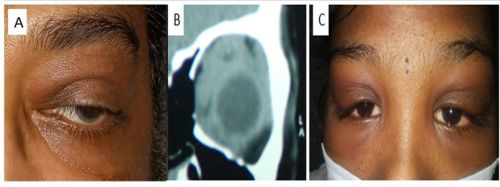

Generalized lid edema may present a diagnostic challenge. Lid edema can be due to trivial local conditions like hordeola or insect bites, but it can also be the presenting sign of systemic disease or neoplasia. Causes of lid edema can be vision-threatening or even life threating, which needs a systematic approach to reach the diagnosis and prompt treatment

The differential diagnosis of lid edema is broad, and the etiology can be sub-grouped into broad categories:

•Infectious •Inflammatory •Allergic/anaphylactic •Vascular •Neoplastic •Trauma •Age related •Systemic causes •Miscellaneous

E. Neoplastic